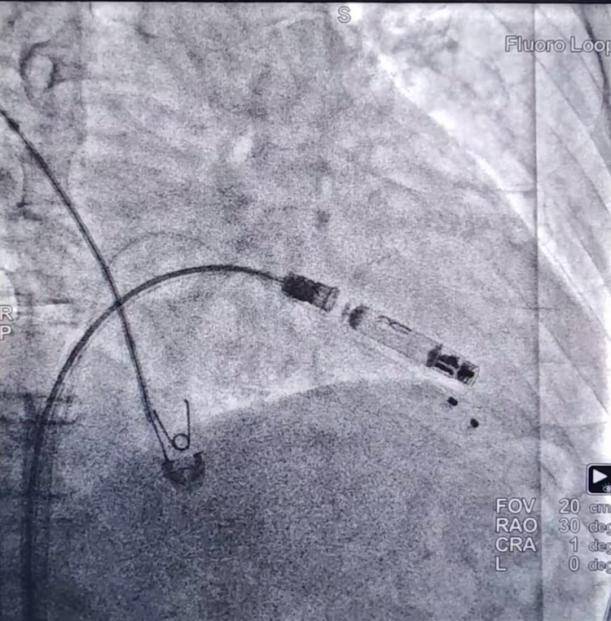

完善相关术前准备,手术由心血管内科蒲晓群教授、江斌主任共同操作。术中经患者大腿根(股静脉)这一微创路径,通过造影确认,精准将心室无导线起搏器植入右心室低位间隔,再将心房无导线起搏器通过递送导管置入右心耳基底部,张力测试后顺利释放。术后患者各项指标良好,i2i通讯流畅,房室同步性表现优异。